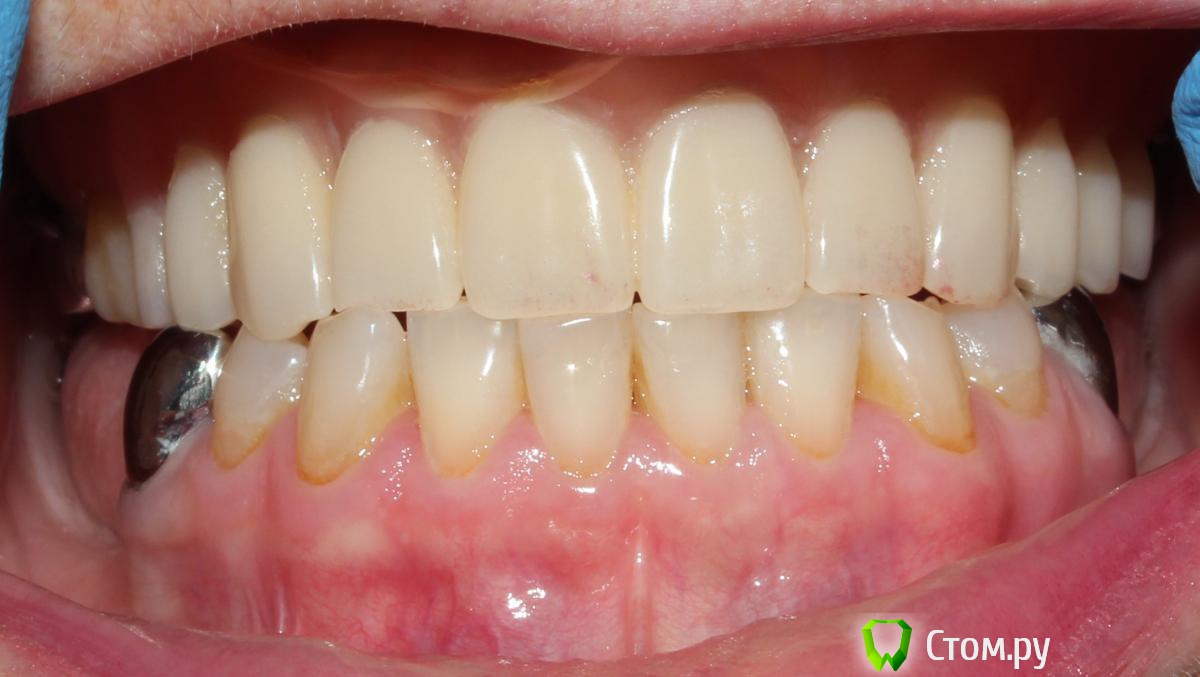

SDC Опубликовано 19 октября, 2014 Поделиться Опубликовано 19 октября, 2014 Балочная или мостовидный протез - покажет восковое планирование и характер улыбки пациентки. Ссылка на комментарий